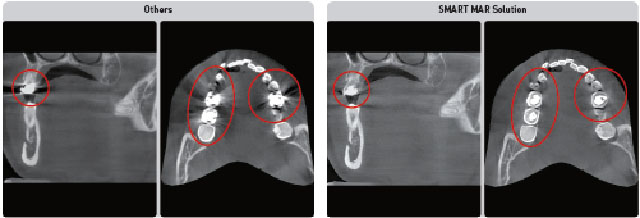

MAR Smart

Medicii doresc să stabilească diagnosticul cu un CBCT care nu se lasă afectat de artefacte metalice în timp ce produce imagini de înaltă calitate 3D. SMART Metal Artefact Removal oferă această facilitate puternică utilizatorilor săi.